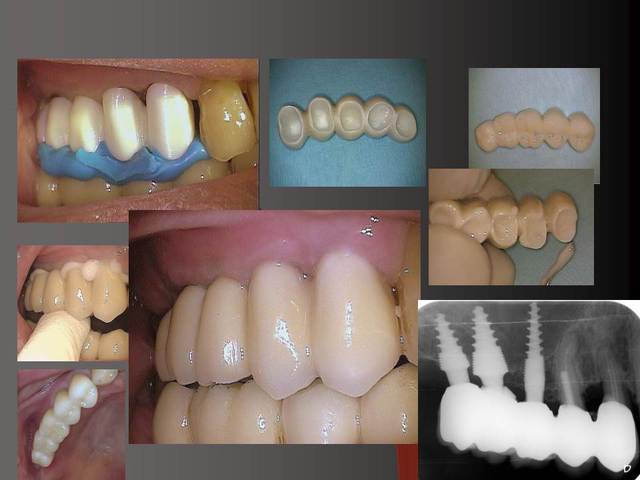

J´ai mis des photos pour mieux voir....

Merci pour ta remarque.C´est vrai que cela est mieux si on ne prérare pas ou presque pas les prep cap à cause des shippings . Normalement je ne les prépare pas, je choisis une forme (avec angle et longueur diiférents) selon le cas et ensuite je les cémente.

je vais ajouter des autres photos ( c´est mieux pour moi de expliquer avec des photos... :-))

Oui sans condenser juste en flapless ca serai moins évident. Pour moi-même en condensant j´ai besoin de 1 mm buccal minimum(plus il y a mieux c´est) mais dans ma pratique et celles mes confrères ca fonctionne et cela dure dans le temps depuis 16 ans.

En dessous il y a des photos, dans une on voit (troisième) qu il n y a pas de resorption de l´os après 14 ans, ce que l´on voit c´est l´os très fin condensé sur l´implant.

Le premier photo c´est une erreur parce que le périoste est blessé et les foret "trop" grands.

Pour la zircone les laboratoires ont le choix entre des rounds isostatiques ou axial pressés, pour moi même je préfère le isostatique car il y a beaucoup moins de shipping :-)